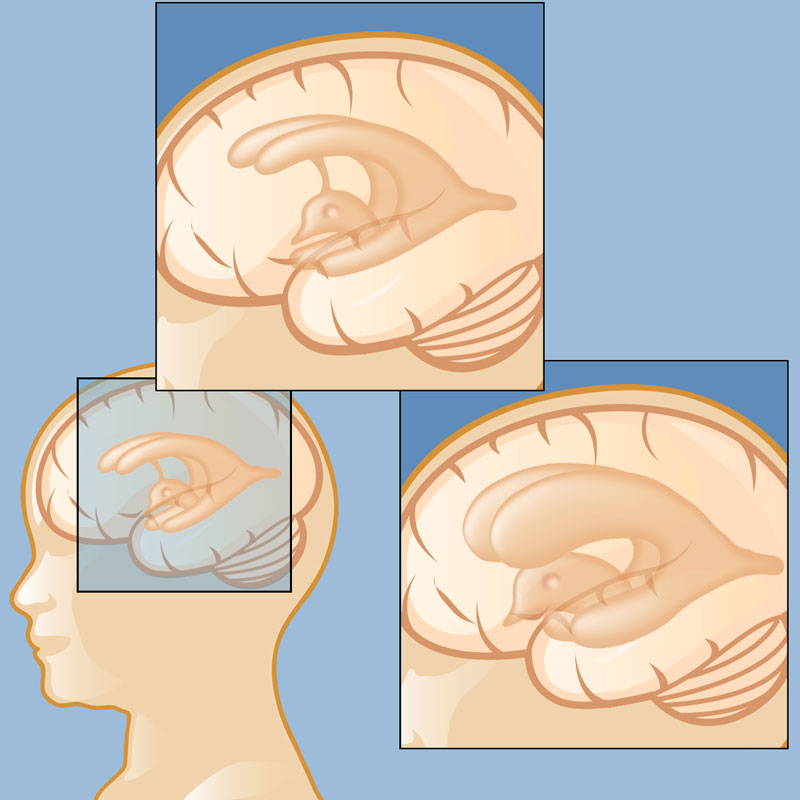

Hydrocephalus in Children and Adults | Neupsy Key

Hydrocephalus in Children and Adults | Neupsy Key

Hydrocephalus in Children and Adults | Neupsy Key